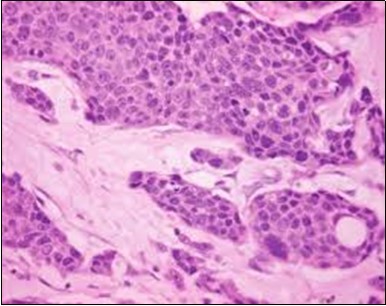

The neoplasm is composed of lobules of aberrant epithelial cells configured in cords with incrimination of the dermis and epidermis.. Malignant cells congregate within the epidermis or infiltrate the dermis, especially in the primary tumour. Tumour cells within tumour aggregates display a well demarcated cellular outline and appear distinct from encompassing squamous cells. Numerous tumour cell clusters demonstrate a cystic lumen. Prominent epidermal acanthosis is discerned on account of tumour cell proliferation 6, 7.

Granular arrangement of malignant cells and intercellular bridges are conspicuous with the demonstration of nuclear atypia, pleomorphism, prominent mitosis and tumour necrosis. A peripheral palisade is discernible within the cellular aggregates. Mitotic figures are common and can be quantified as up to 12 mitosis/ high power field. Tumour differentiation can prominently be of the ductal category with the demonstration of intra-cytoplasmic lumina. Comedo type tumour necrosis is evident along with foci of squamous differentiation The neoplasm is reactive to periodic acid Schiff ‘s (PAS) stain. (Figure 1, Figure 2, Figure 3, Figure 4, Figure 5, Figure 6, Figure 7, Figure 8, Figure 9, Figure 10, Figure 11, Figure 12, Figure 13.

Figure 1.Solid aggregates of tumour cells and duct structures in eccrine porocarcinoma (14).

Figure 2.Epidermal projections lined with atypical and malignant epithelial cells in eccrine porocarcinoma (14).

Figure 3.Cohesive accumulations with numerous ductular articulations of carcinoma cells in eccrine porocarcinoma (15).